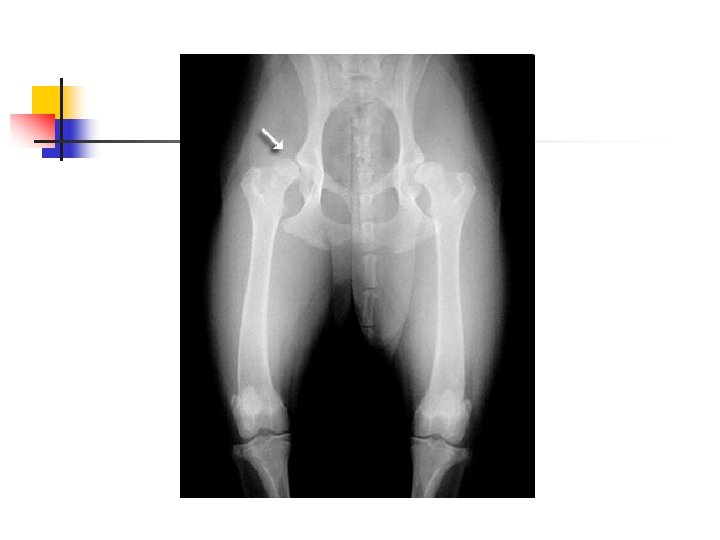

Hip Dysplasia n n Hip dysplasia is a looseness in the hip joint. The hip is a ball-and-socket joint and the head (ball) of the femur (thigh bone) normally should be deep within the hip socket. When hip dysplasia is present, the ball moves in and out of the socket with ease. Over time arthritis (degenerative joint disease, osteoarthritis) sets in as the body tries to stabilize the loose joint.